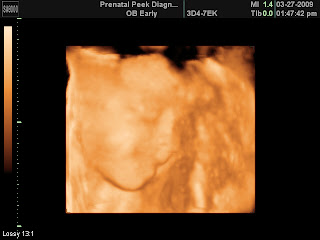

So this past weekend, Preston and I went to North Carolina to see our family and the newest addition! Leah is so very pretty and Jacob is one handsome little (well, actually quite big) man. We had a short but great visit with them. Leah is growing so fast and I hate that we don't get to see them more often. Well, while we were I got to get an ultrasound at 27 wks. It was such a great experience and so much fun! Ezri is growing so much. It was so neat to see her up close like that and to see her personality. She is quite stubborn and I have no idea where she gets that from! We did find out that my placenta has moved and we should not have to worry about that anymore! That was such a relief! Well, I hope everyone enjoys the pics of Ezri- courtesy of Prenatal Peeks and my wonderful sister-in-law Katie! Also, my next appointment is April 1, so I will let everyone know how it goes!